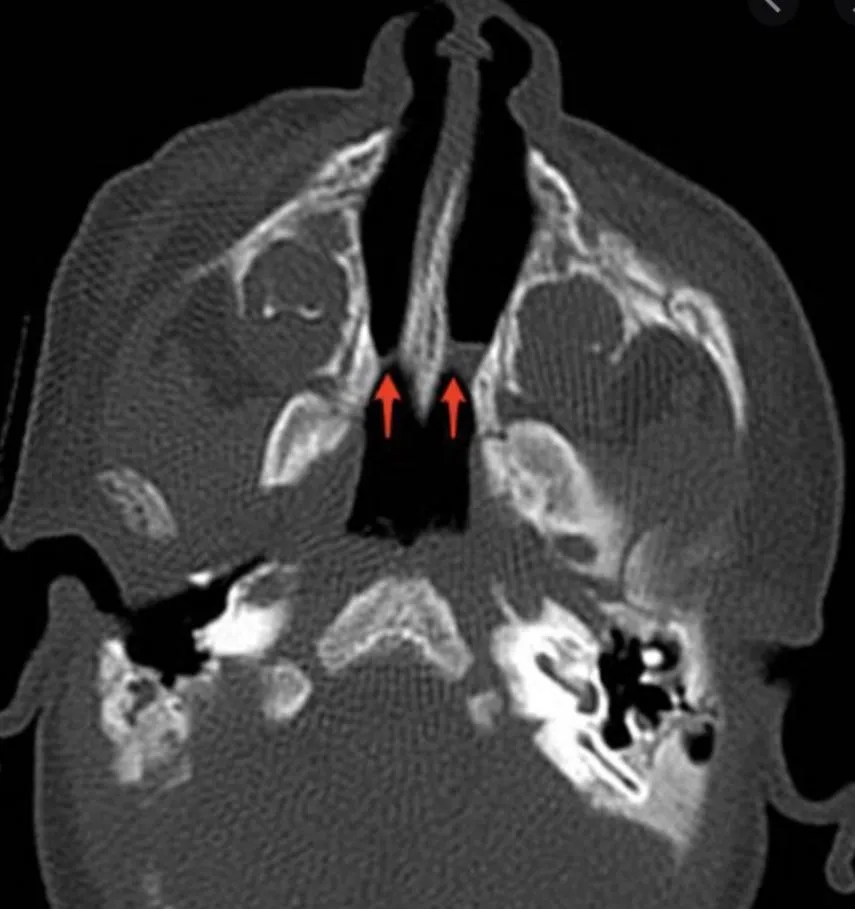

Bilateral Choanal Atresia

A newborn baby presented with cyclical cyanosis immediately after delivery, with an inability to pass nasal suctioning in both nostrils for more than 5 cm. - Diagnosis: Bilateral Choanal atresia. - Initial Emergency Management: Oral Airway.

A patient delivered a few minutes prior presented with cyclical cyanosis and desaturation that improved with crying. A size 6 French catheter could not be advanced more than 5 cm. - Diagnosis: Bilateral choanal atresia. - Confirmation: CT scan.